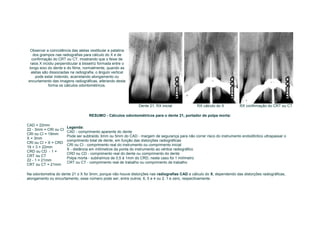

RESUMO - Cálculos odontométricos para o dente 21, portador de polpa morta:

CAD = 22mm

22 - 3mm = CRI ou CI

CRI ou CI = 19mm

X = 3mm

CRI ou CI + X = CRD

19 + 3 = 22mm

CRD ou CD - 1 =

CRT ou CT

22 - 1 = 21mm

CRT ou CT = 21mm

Na odontometria do dente 21 o X foi 3mm, porque não houve distorções nas radiografias CAD e cálculo do X, dependendo das distorções radiográficas,

alongamento ou encurtamento, esse número pode ser, entre outros, 6, 5 e 4 ou 2, 1 e zero, respectivamente.